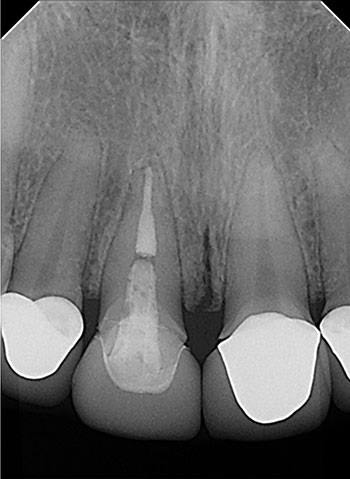

Case 5: Bilateral lesions

This patient was very worried that she was going to lose her front tooth, #8. Her dentist was concerned that the root had been split by a large, tapered post given the context of the bilateral radiolucencies located at the bottom of the post.

No crack was seen when the post was removed, nor were any lateral canals located. This tooth was treated in three visits over six months using a calcium hydroxide intracanal medicament. It is possible that a nidus of bacteria remained in the gap between the obturation and the post.

The patient’s symptoms resolved after the first visit. The case was obturated after confirming full bony healing. She is still extremely appreciative of the efforts made to save her front tooth.

Endodontic Root Fracture Case Series

Fig. 19: Preop PA.

Fig. 20: Preop CBCT.

Fig. 21: Recall PA.

Fig. 22: Recall CBCT.